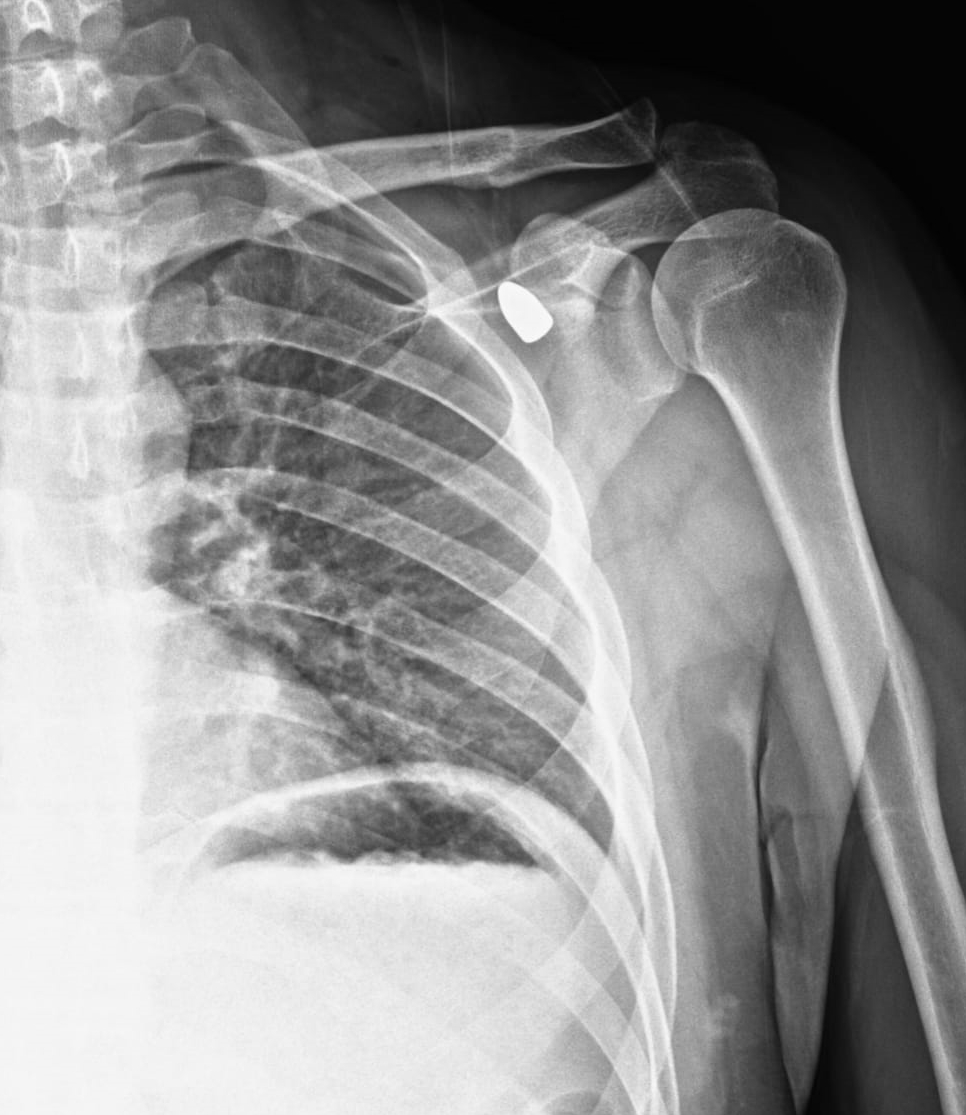

Konya’da okul müdürünün vücudundaki yorgun mermi 6 yıl sonra çıkarıldı

Konya’nın Akşehir ilçesinde altı yıl önce bir okul müdürünün omzuna isabet eden yorgun mermi tıbbi müdahaleyle çıkarıldı.

Okul müdürü Celal Şenyiğit, Adsız Mahallesi'ndeki çay ocağında, altı yıl önce omzuna isabet eden yorgun mermiyle yaralandı.

Hareket kaybı riski nedeniyle çıkarılamayan mermi, zamanla Şenyiğit'in koltuk altına ilerledi. Ağrı ve sertlik şikayetiyle Akşehir Devlet Hastanesine başvuran Şenyiğit'in koltuk altındaki kitlenin, omzuna saplanan yorgun mermi olduğu tespit edildi.

Mermi, gerçekleştirilen operasyonla çıkarıldı.

Şenyiğit, olayla ilgili şikayetçi olduğunu, çıkarılan merminin incelemeye gönderildiğini söyledi.